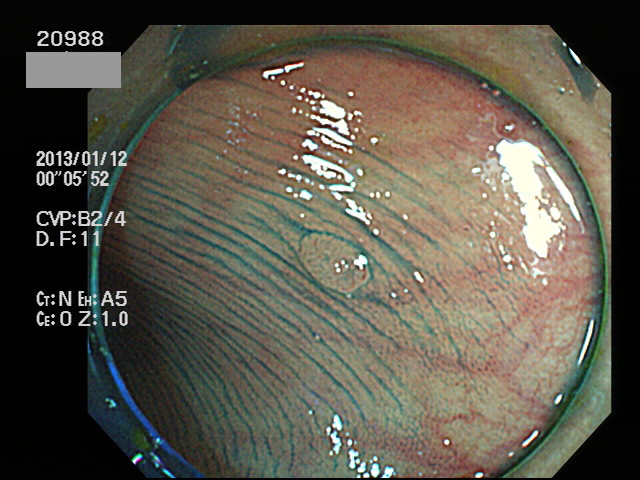

1ミリの高度異型腺腫(癌化の直前の病変)